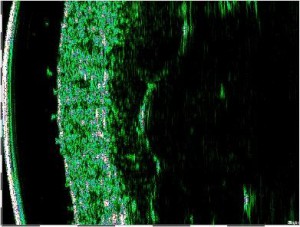

Σάρωση άθικτου δέρματος στα 75 MHz (αριστερά) και διάγραμμα της μικροανατομικής δομής του δέρματος (δεξιά).

e – επιδερμίδα, pd – θηλώδες χόριο, rd – δικτυωτό χόριο, hf – θύλακας της τρίχας, bv – αιμοφόρο αγγείο βαθέος δερματικού πλέγματος, λίπος – λιπώδης ιστός, fas – περιτονία, msc – μυς.